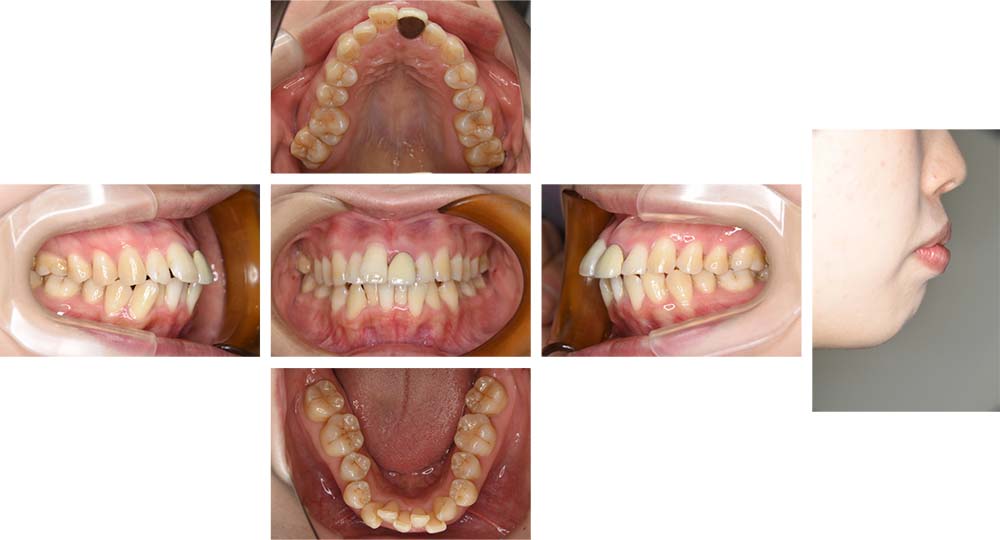

治療前

治療後

上顎左側側切歯の口蓋側転位を主訴としてご来院いただいた。初診時ご相談時には口元に対しての要求はなかったが、口元の突出(俗にいうゴボ口)とガミースマイルについての説明をしたところ、治療対象とすることを希望された。セファログラムの分析の結果、上下顎前突と診断した。上下顎小臼歯抜歯を行っていただき、矯正用アンカースクリューを併用し唇側マルチブラケット装置を使用して動的治療を行った。上下顎前歯の後退が十分行われ口元の突出感も改善した。上口唇はE-ラインから2㎜後退し、下口唇もほぼE-ライン上へ後退させ美しい口元の形態とすることができた。また、前歯の後退方向にも工夫を行ったことから、ガミースマイルについても軽減した。動的治療期間2年2カ月間。